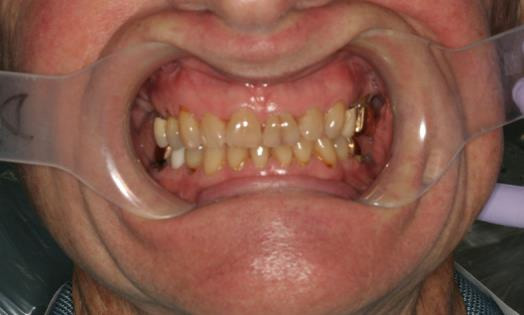

Intraoral clinical exam

- Palate: Normal

- Tongue: slightly coated with normal range of motion and no lesions

- Floor of mouth and mucosa appears normal with no lesions

- Teeth with exposed root surfaces from gingival recession

- Discoloration of teeth

- Supraerupted teeth

- Missing teeth - #1,3, 13, 16, 17 18, 19, 31, 32

- Clenching/grinding/ parafunctional habits

- Abfractions

- Wear facets on posterior teeth and restorations

- Craze lines – prominent on #8 and 9

Final Intraoral Photographs